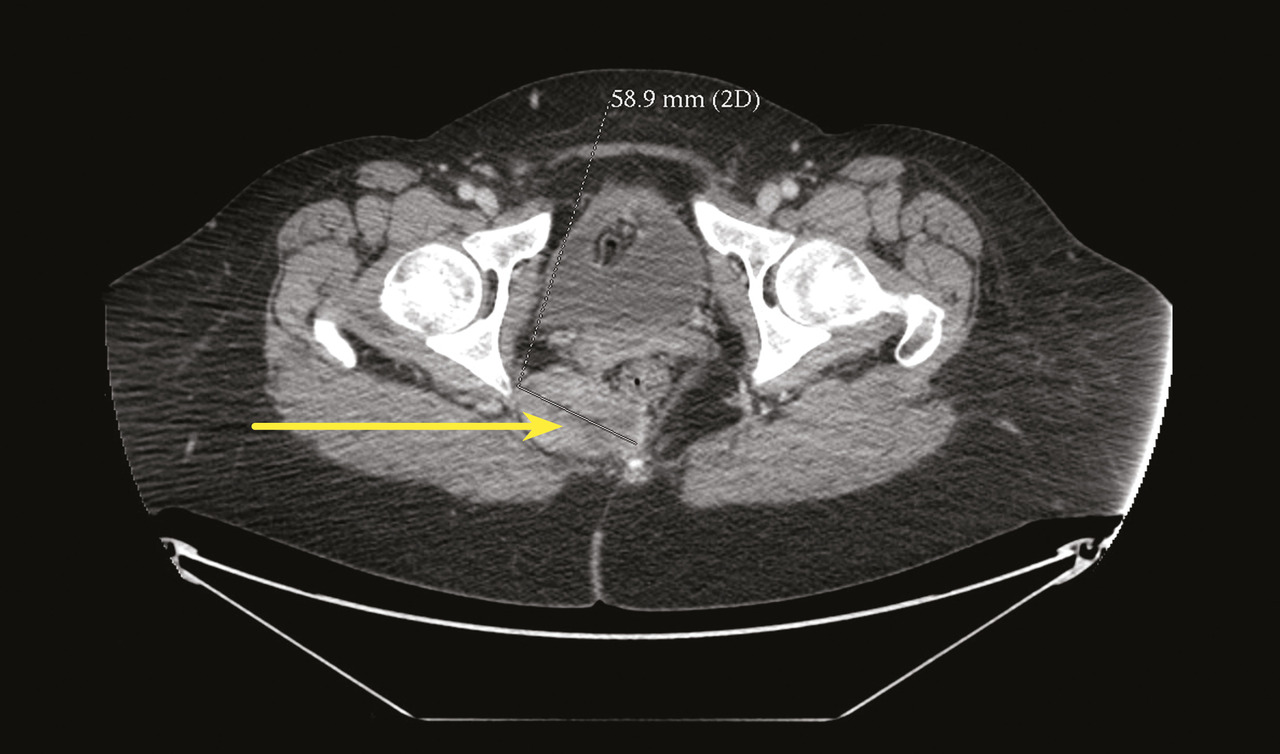

Certains phénomènes compressifs peuvent être à l’origine de NP, comme les contractures myofasciales des muscles de voisinage (muscle obturateur interne ou muscle piriforme) et certains processus tumoraux, qui bien qu’exceptionnels, doivent toujours être recherchés, imposant la réalisation d’une imagerie par résonance magnétique (IRM) ou d’un scanner pelvien (fig. 4).